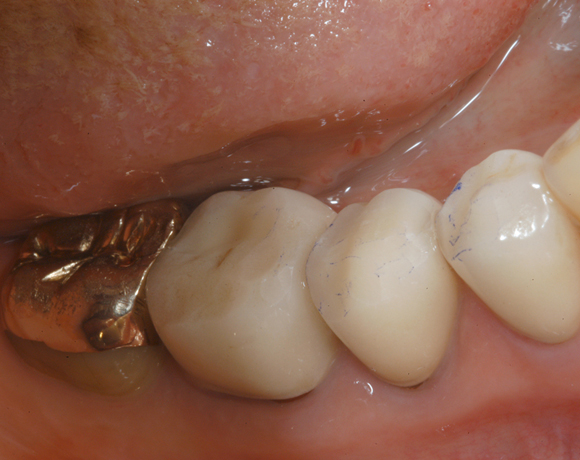

22 Einzelkronen mit Eris for E II

Empress II Presskeramik mit Eris Verblendkeramik bei einer Neuversorgung im Oberkiefer komplett und im Unterkiefer Vollkronen auf den Seitenzähnen.

Ein Projekt aus dem Jahr 2004

Hier wurden der ganze Oberkiefer und die Seitenzähne im Unterkiefer mit neuen Kronen aus Empress 2 und mit Eris Verblendkeramik versorgt.